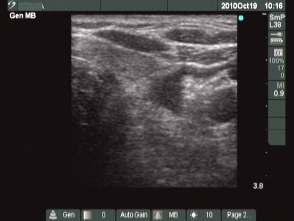

Third session (third row of images):

Clinical presentation: the patient had no complaints. The patient has ceased to cough.

I injected 1 mL ethanol.